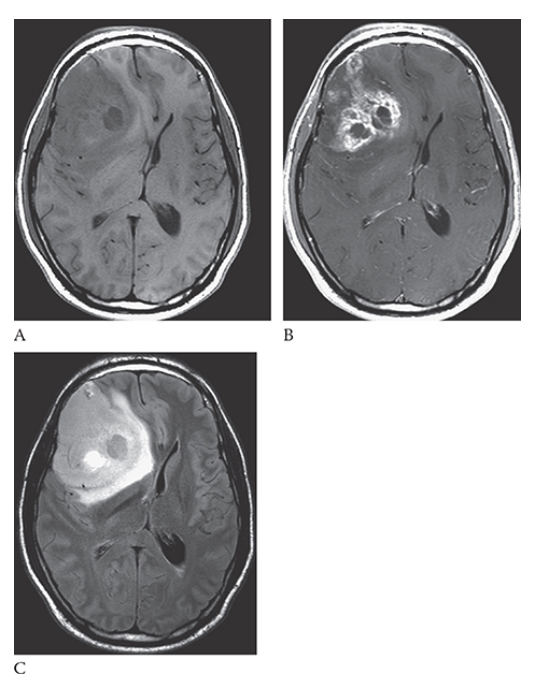

What is A

Intracerebral Hemorrhage. Axial NECT image shows an acute hemorrhage in the left posterior parietal lobe. Note the blunting of the left ventricle. An axial T1W image

What is B

Intracerebral Hemorrhage. Axial NECT image shows this area as isointense to hypointense. T2W axial image

What is C

Intracerebral Hemorrhage. Axial NECT image shows the blood to be mildly hyperintense. Gradient echo axial MR

What is D

Intracerebral Hemorrhage. Axial NECT image shows the blood products to be hypointense.